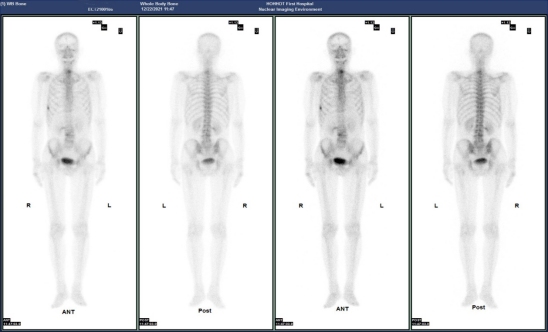

(病例三)患者,男 44岁,左肺下叶恶性肿瘤(T4N2M1c,IVB),纵膈继发性恶性肿瘤,胸膜继发性恶性肿瘤,骨和骨髓继发性恶性肿瘤。靶向药物治疗后为评估骨继发恶性肿瘤来诊。MIP图示:与2021-8-3日片比,2021-12-21日片示左侧第8后肋病灶放射性摄取明显减低,左侧第3后肋、胸骨柄片状放射性摄取范围减小,右侧第6前肋、L2椎体放射性摄取范围无明显变化。结论:与2021-8-3日片比:左侧第8后肋、左侧第3后肋、胸骨柄病灶骨盐代谢明显减低,提示肿瘤细胞活性减低;右侧第6前肋、L2椎体病灶骨盐代谢无明显变化。